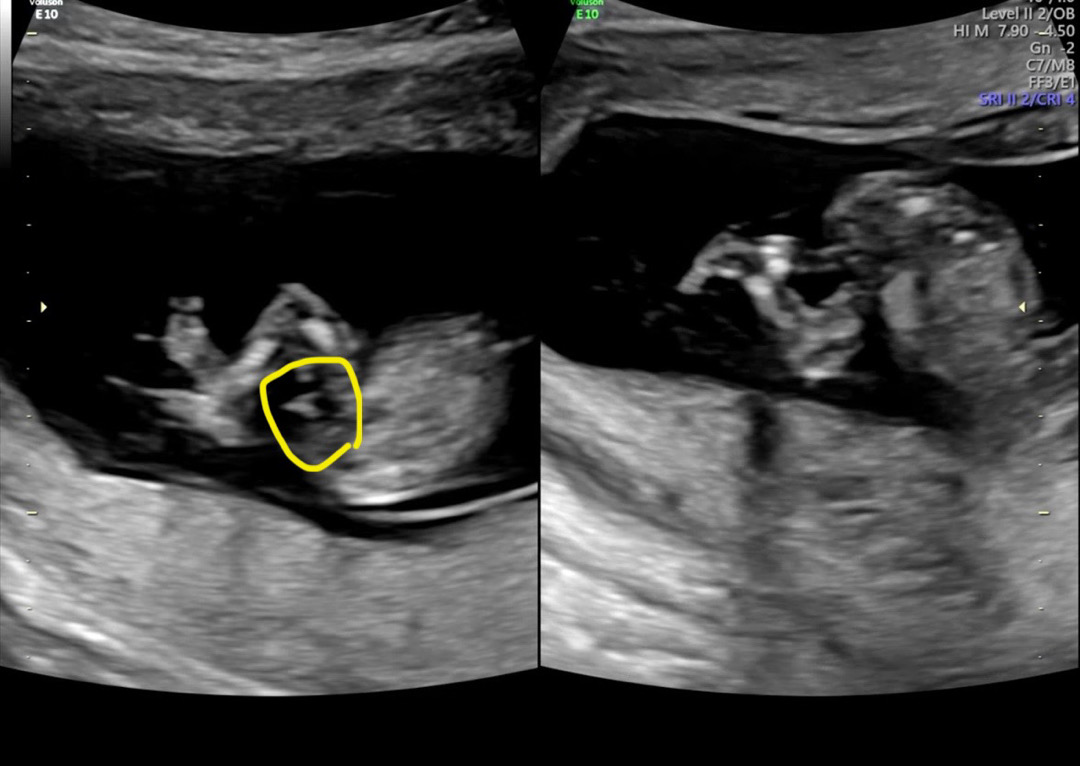

꼬츄일까요...???

12주 정밀 초음파 보면서 발견한건데ㅋㅋㅋ 선생님은 별 말 없으시긴 했지만 동영상을 돌려보다 보니 다리를 꼬고 있는 사이로 뭔가 삼각점같은 무언가가 보이는 것 같아서요!!